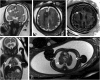

Human cytomegalovirus (CMV) is an ubiquitous pathogen, with a high worldwide seroprevalence. When acquired in the prenatal period, congenital CMV (cCMV) is a major cause of neurodevelopmental sequelae and hearing loss. cCMV remains an underdiagnosed condition, with no systematic screening implemented in pregnancy or in the postnatal period. Therefore, imaging takes a prominent role in prenatal diagnosis of cCMV. With the prospect of new viable therapies, accurate and timely diagnosis becomes paramount, as well as identification of fetuses at risk for neurodevelopmental sequelae. Fetal magnetic resonance imaging (MRI) provides a complementary method to ultrasound (US) in fetal brain and body imaging. Anterior temporal lobe lesions are the most specific finding, and MRI is superior to US in their detection. Other findings such as ventriculomegaly, cortical malformations and calcifications, as well as hepatosplenomegaly, liver signal changes and abnormal effusions are unspecific. However, when seen in combination these should raise the suspicion of fetal infection, highlighting the need for a full fetal assessment. Still, some fetuses deemed normal on prenatal imaging are symptomatic at birth or develop delayed cCMV-associated symptoms, leaving room for improvement of diagnostic tools. Advanced MR sequences may help in this field and in determining prognosis, but further studies are needed.